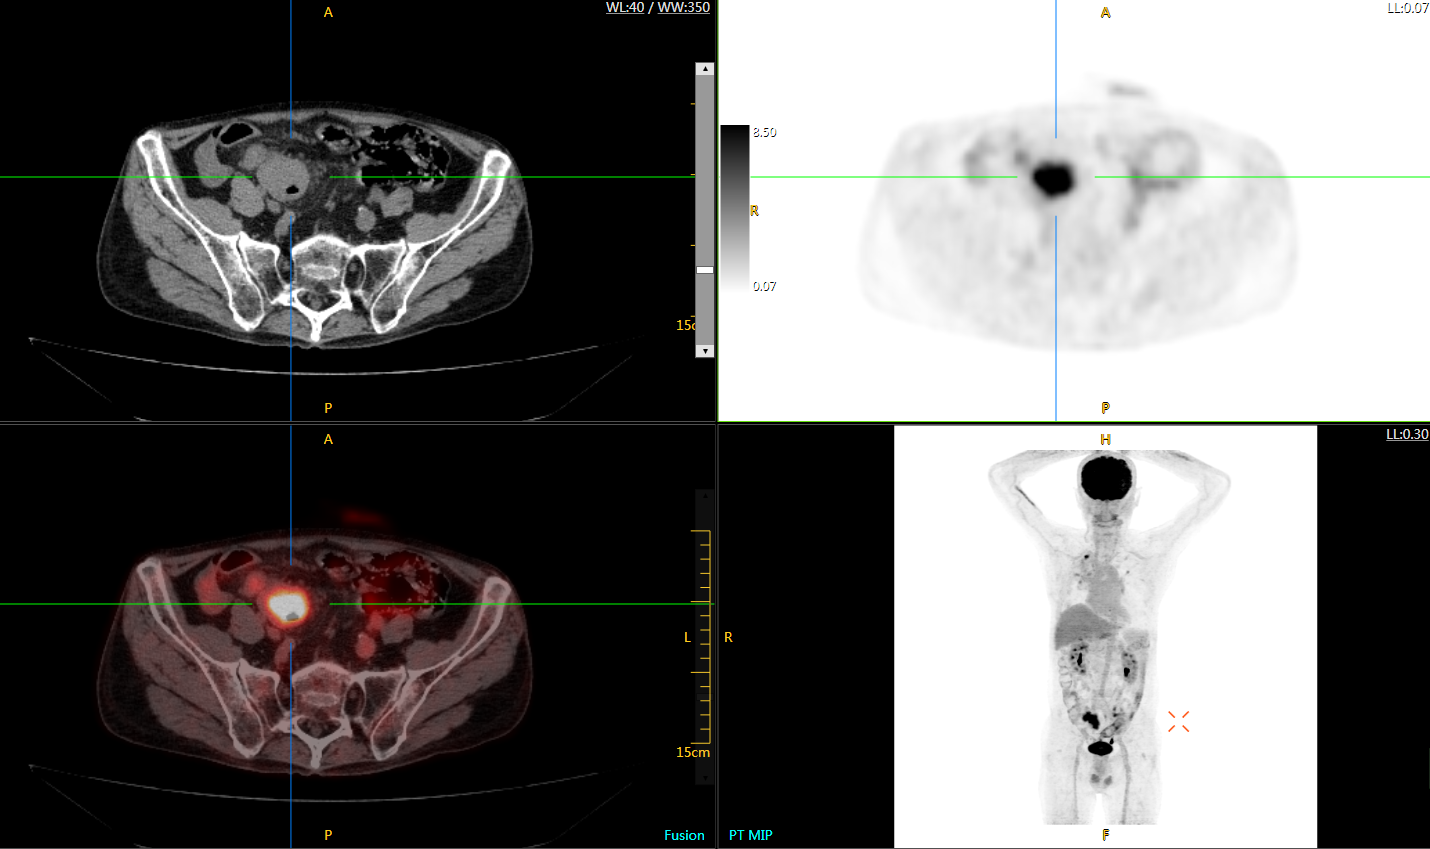

注射總劑量為0.67 mCi FDG(低于常規(guī)劑量的十分之一),基于uEXPLORER探索者掃描15分鐘的圖像

注射總劑量為6.9mCi,注射后10小時(shí),基于uEXPLORER探索者掃描14分鐘的圖像